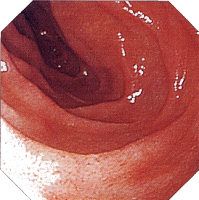

内視鏡所見

縦走潰瘍 敷石像 不整形潰瘍

クローン病画像 クローン病画像 クローン病画像

提供:牧山和也先生